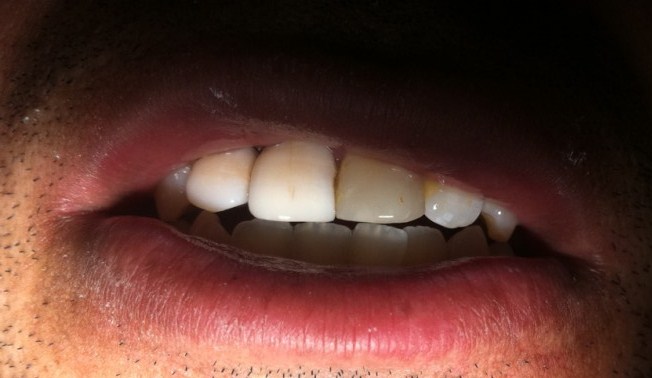

Ficaram mais claros, óbvio, estavam desidratados! Ficou um pouco desalinhado na hora, então foi necessário realizar alguns ajustes.

E finalizando os ajustes, ficou assim: